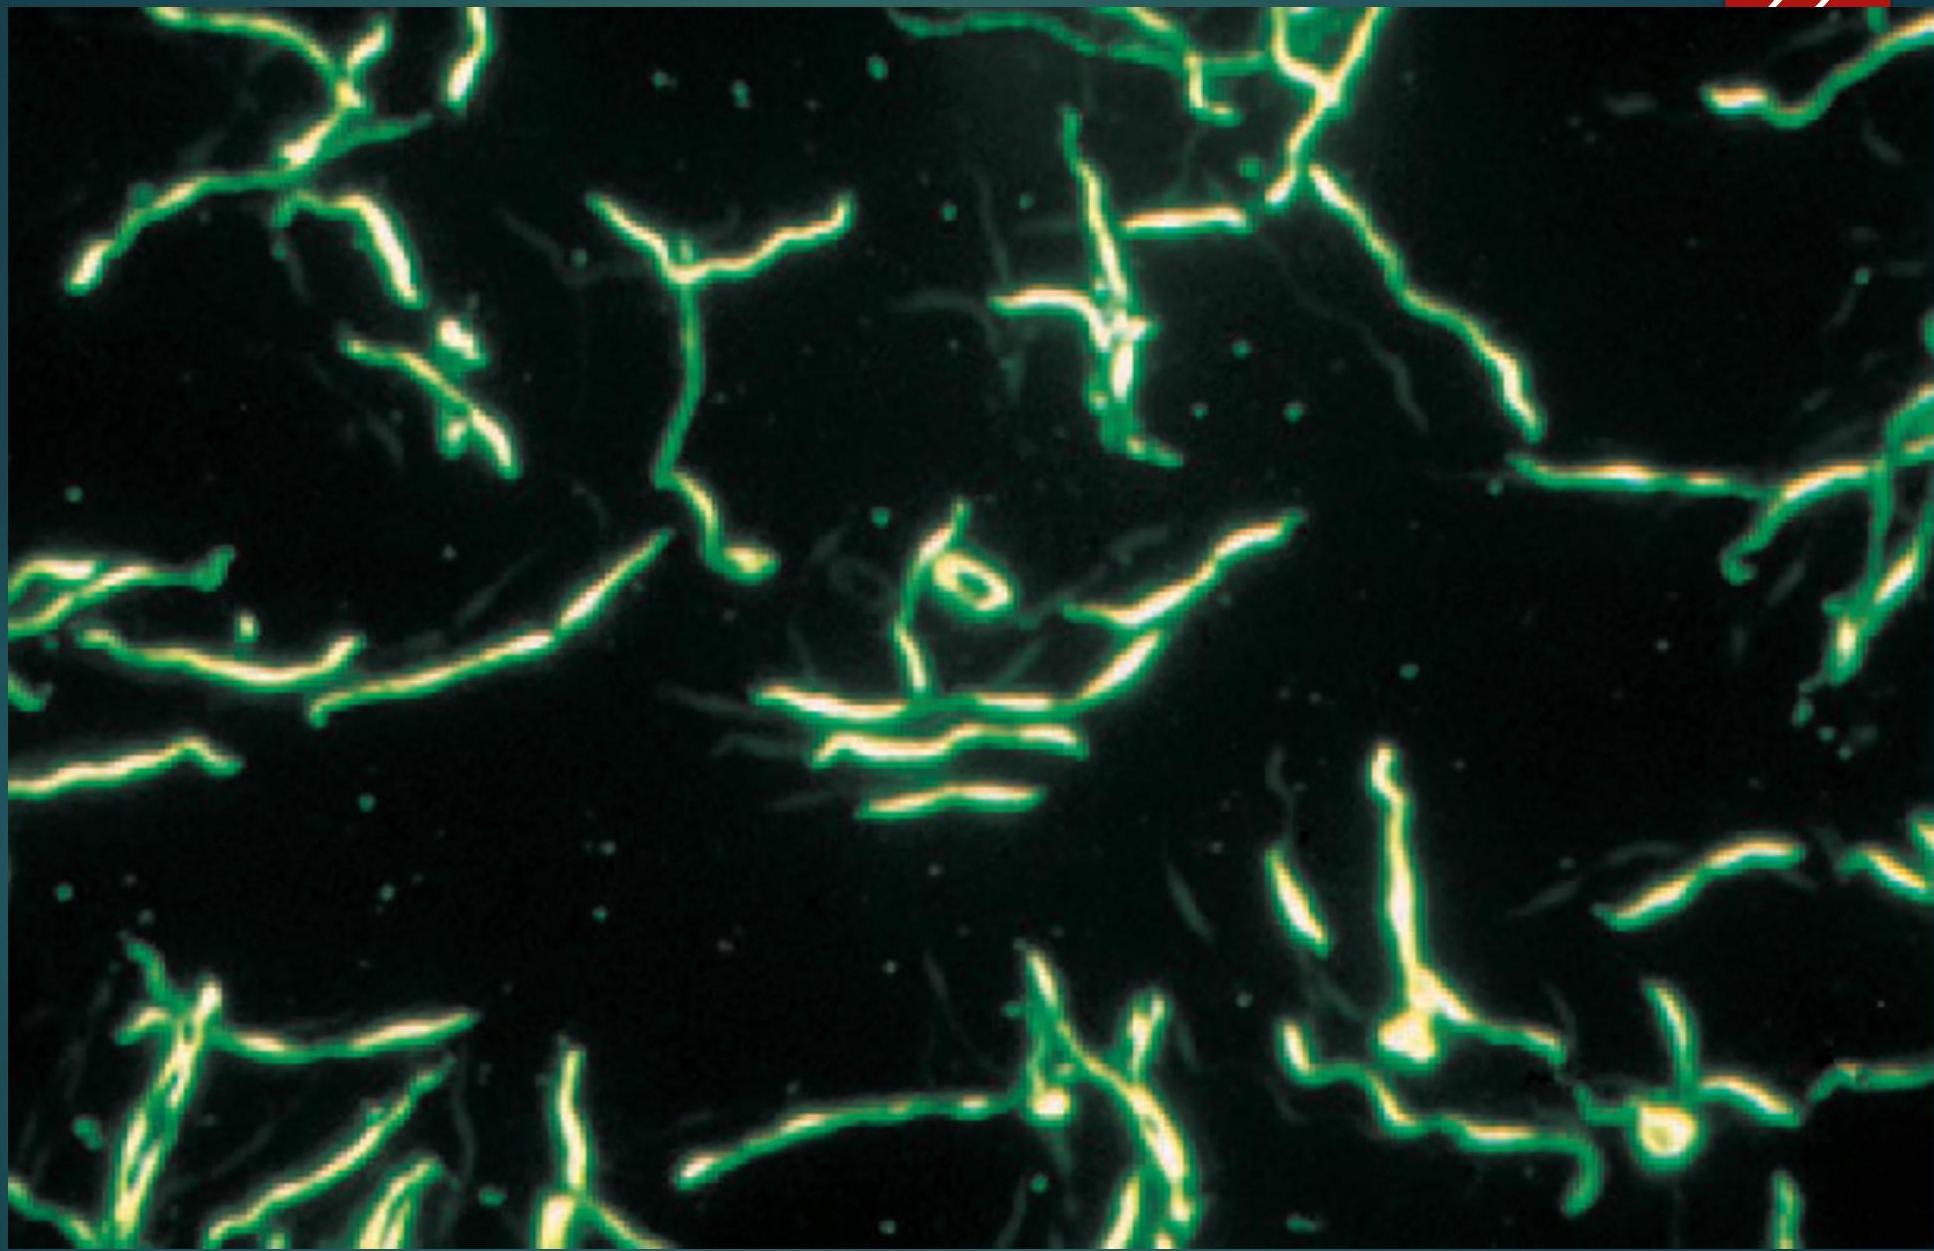

Photomicrograph of Treponema pallidum, as Seen with Dark-field Microscopy

- Most sensitive method of identification is dark ground microscopy – organism is found in primary chancre